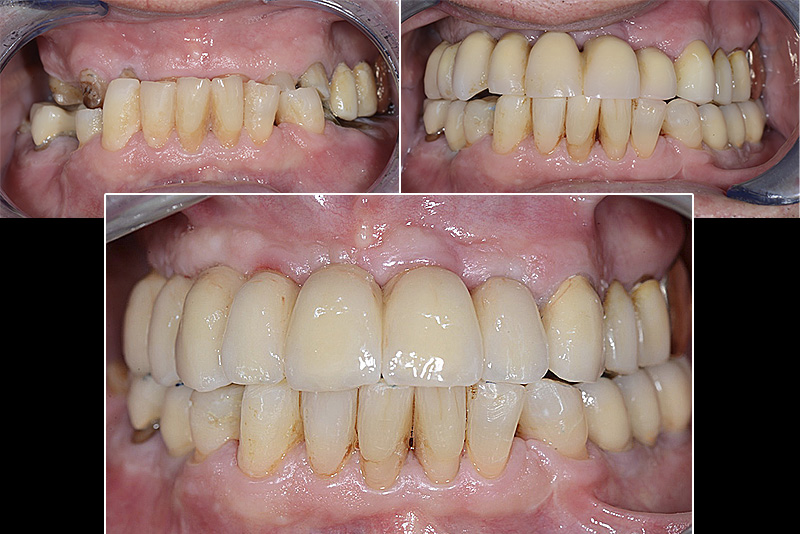

PREMESSA: in seguito all’estrazione dell’incisivo laterale superiore di destra, resasi necessaria per cause batteriche, si decide di affrontare il caso con il posizionamento di un impianto in sostituzione dell’elemento mancante dopo guarigione del sito infetto. Con tecniche rigenerative sia dei tessuti ossei mancanti a causa dell’infezione pregressa, sia dei tessuti gengivali che appaiono inizialmente troppo spostati in alto, si ripristina una corretta morfologia delle parabole (contorni) gengivali e delle papille interdentali (triangoli di gengiva tra due denti vicini).

Vengono utilizzati 2 tipi di provvisori: il primo, cementato ai denti vicini, viene utilizzato dal momento dell’estrazione del dente fino ad impianto osteointegrato (circa 6 mesi); il secondo, avvitato direttamente all’impianto, ha una funzione di prova estetica ma soprattutto di guida per la maturazione dei tessuti gengivali peri-implantari portandoli verso la maturazione completa prima di posizionare la corona finale in disilicato di litio.